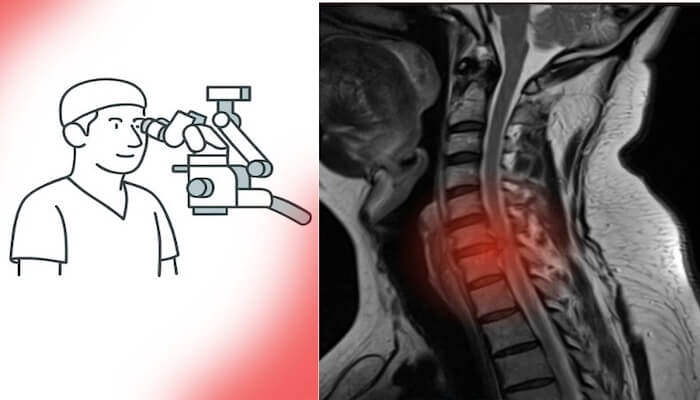

Beyin ve Omurga Cerrahisinde Hasta Profili Değişti: Genç Yaşta Ameliyatlar Artıyor

Son yıllarda beyin ve omurga cerrahisinde hasta profili belirgin biçimde değişti. Artık ameliyat masasında sadece ileri yaşlı hastalar değil, genç erişkinler de yer alıyor. Özellikle bel fıtığı ameliyatı, boyun fıtığı ameliyatı ve hatta beyin tümörü ameliyatı geçiren hastaların yaş ortalaması giderek düşüyor. Peki bu değişimin sebepleri neler?

Teknolojik Tanı Yöntemleriyle Erken Teşhis

Günümüzde MR ve BT gibi ileri radyolojik görüntüleme yöntemlerine erişim son derece kolaylaştı. Artık neredeyse her şehirde donanımlı hastaneler ve modern tanı merkezleri bulunuyor. Bu sayede en küçük lezyonlar bile erken dönemde saptanabiliyor.

Türkiye’de sağlık hizmetlerine erişim ve radyolojik altyapı son yıllarda ciddi bir ivme kazandı; adeta sağlıkta zirveye ulaşıldı.Bu gelişmeler, tanı sürecini hızlandırarak hem beyin tümörü ameliyatı hem de omurga cerrahisi gerektiren hastaların erken dönemde tespit edilmesini sağladı. Eskiden geç tanı alan birçok vaka, artık uygun zamanda cerrahi müdahaleye yönlendiriliyor. Böylece erken tanı, hem nörolojik kayıpların önlenmesine hem de cerrahi başarı oranlarının artmasına katkı sunuyor.